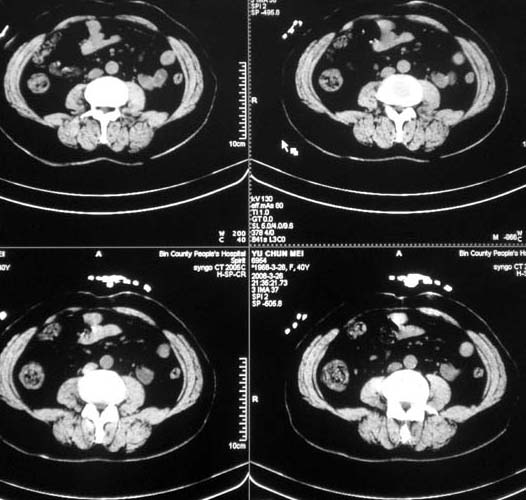

女,56岁,和上两个是同一病人,腹痛,胀痛,消化不良,五年前有血管瘤。密度减低影ct值为40hu。

肝内多发低密度影,边缘清楚,结合病史考虑:肝血管瘤可能性大,建议必须时增强扫描。